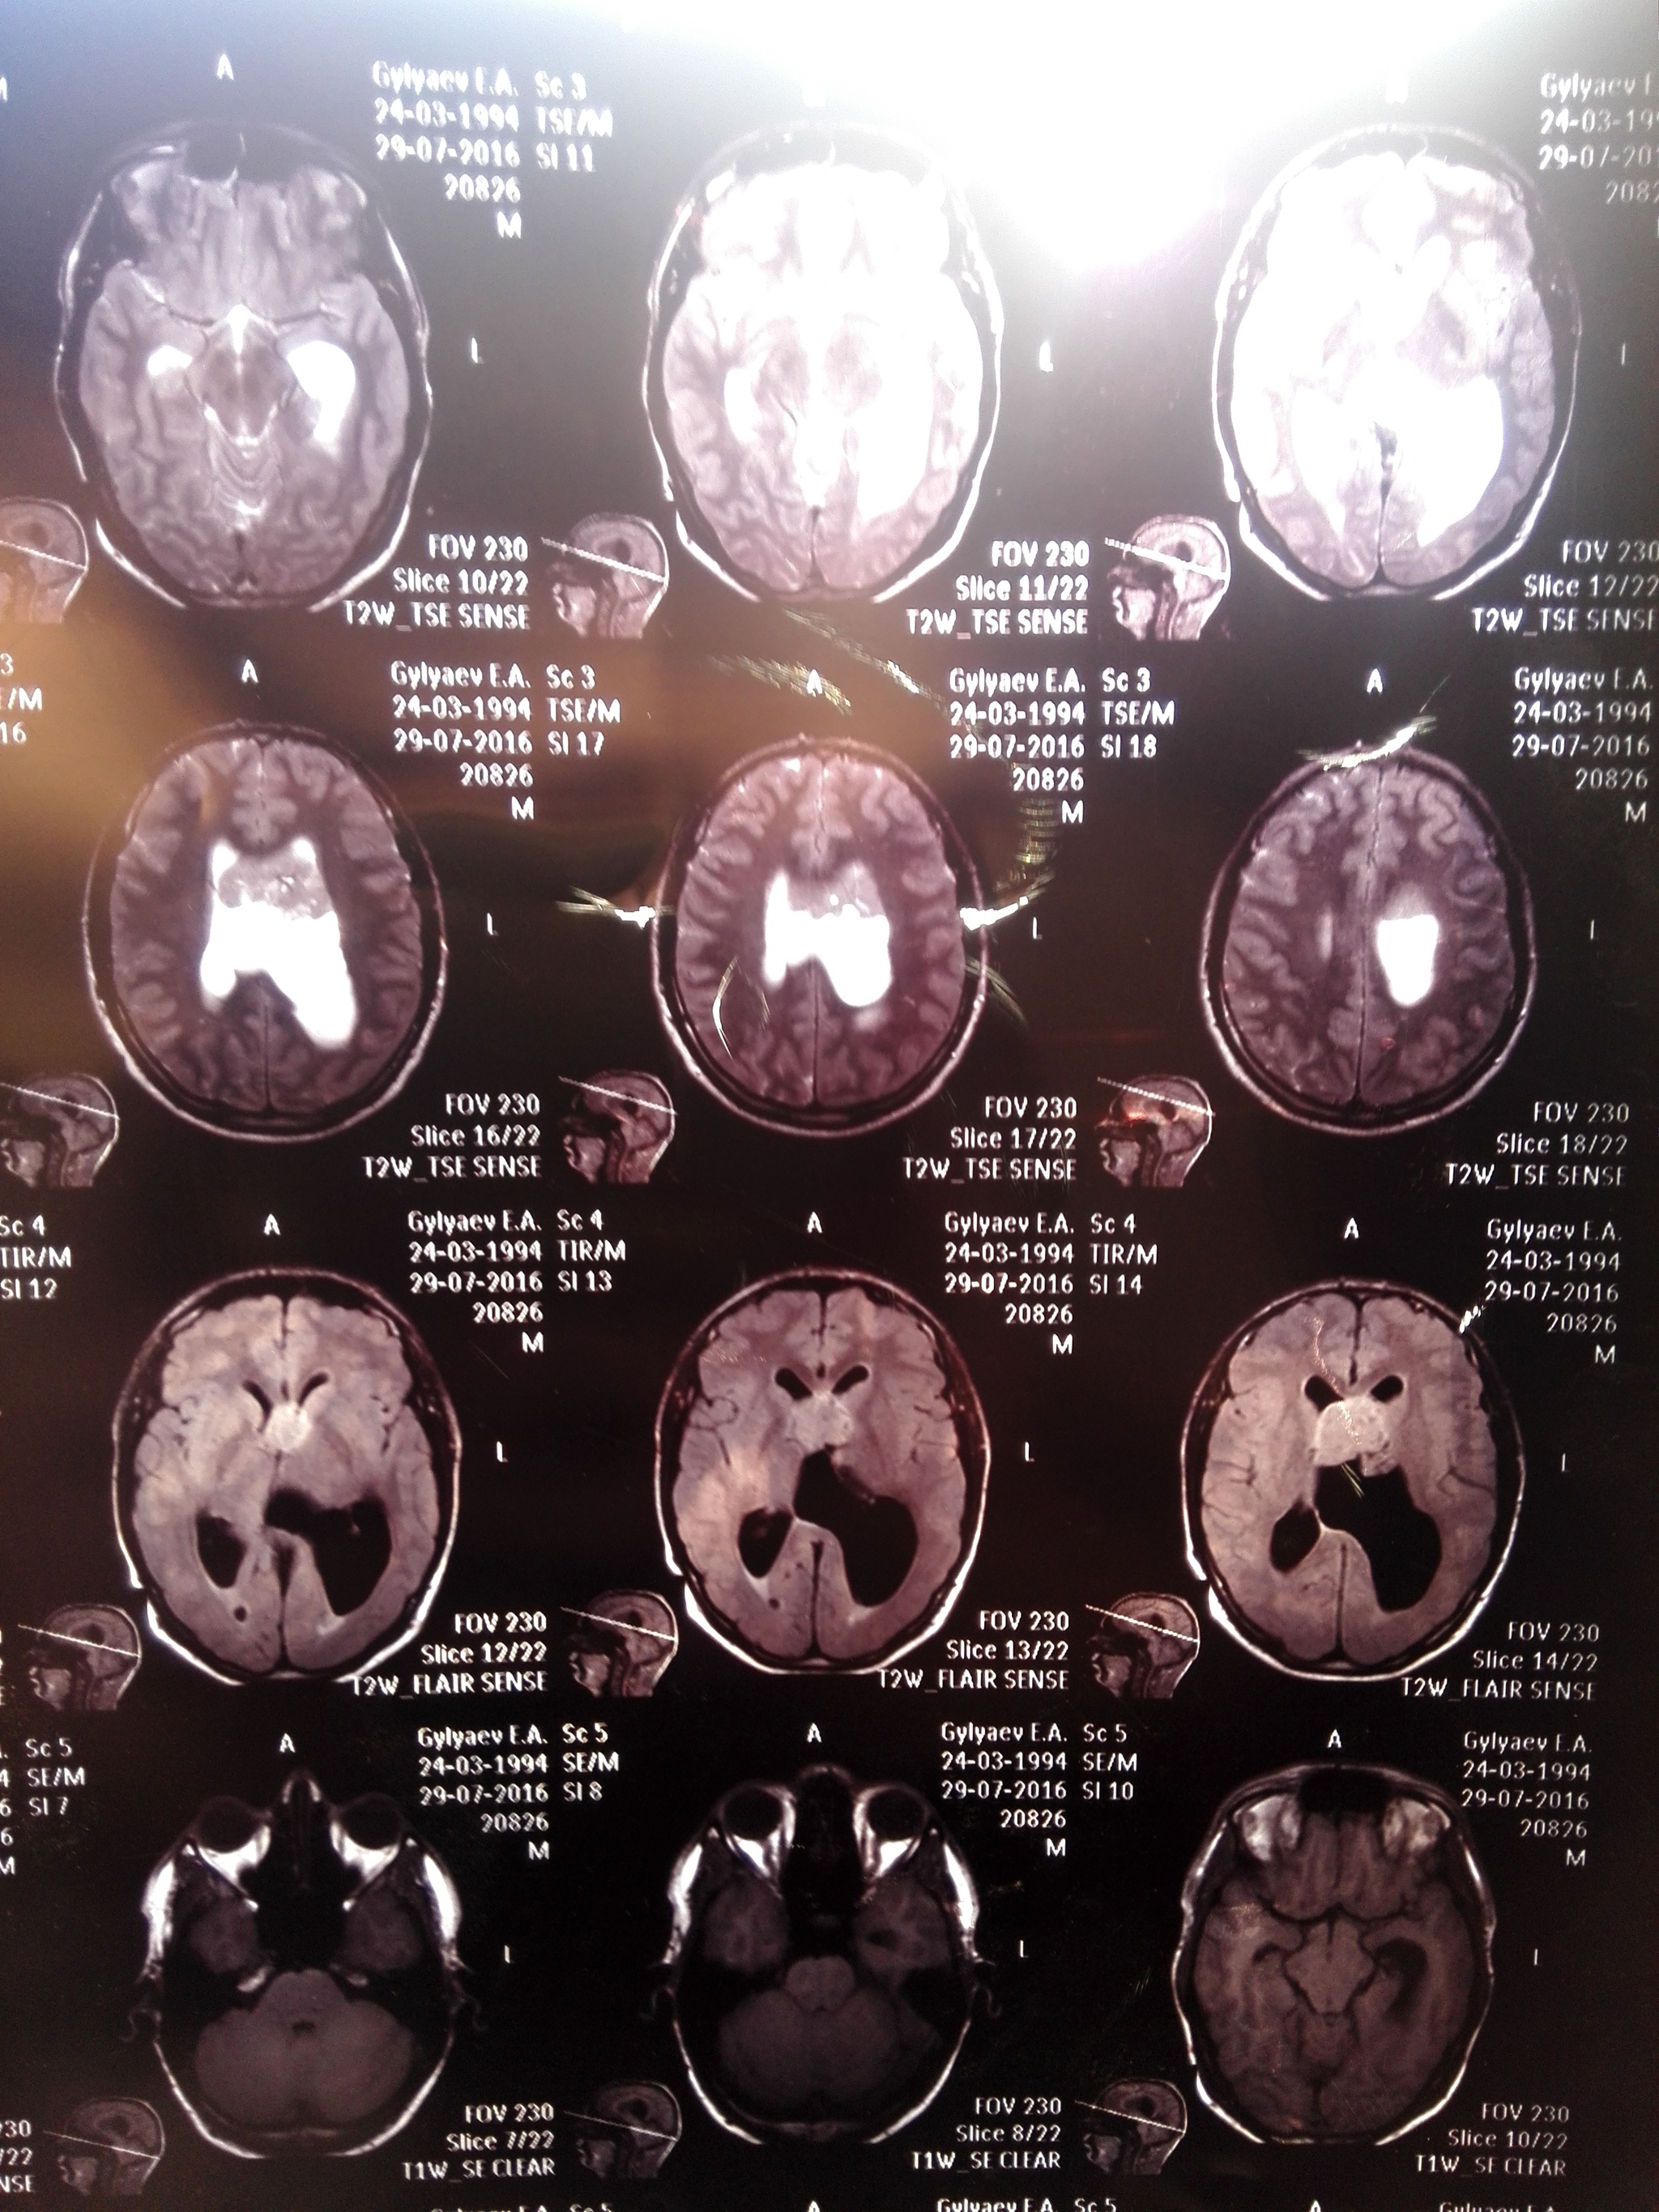

15 ноября ,к слову через день после моего 33 дня рождения я находилась дома одна с новорождённым ребёнком и у меня резко начало гореть лицо , пошло ощущение мурашек по носу и губам , ужасное чувство , помню его как сейчас , через пару часов стало как то сильно плохо и я побежала звать на помощь , добежать смогла до коридора , открыла дверь и нрохнулась в обморок на затылок , до сих пор помню звук как я падаю , перед падением увидела своё лицо в отражении двери, помню, что лицо как то все скривило , потекли слюни и я упала , ещё тогда подумала , что это инсульт и мне хана . Слава Богу свекровь , что живёт по соседству услышала через стену ( стена у нас общая ) грохот,прибежала и вызвала скорую . Повезли меня на скорой на обследование (от которого я изначально упорно отказывалась , так как дома маленький ребёнок, но в итоге поехала ,ещё тогда свято верила , что это просто упадок сил и через пару часов поеду домой , как же я ошибалась . Сделали кучу обследований у всевозможных врачей, потом кт, мрт и мртс контрастом, вот на последнем выясняется ,что у меня опухоль головного мозга ,размером 6см , решают оставить меня больнице на дальнейшее обследование, дальше капельницы ,уколы, день за днём, готовят к операции и переводят в 1ю краевую больницу города Краснодара, туда я поступила вечером , меня сразу побрили на лысо , тупой бритвой ,без пены для бритья , пошкрябали весь череп , следующий день 20.11 к обеду меня увозят на операцию. Операции я не боялась, но ужасно боялась, что будет после , начиталась о последствиях и страшно было, что больше не смогу ходить или говорить и тд , операция прошла без последствий ,опухоль полностью удалили и отправили на биопсию . Состояние после операции ужасное , все болит , голова тяжёлая, обезболивающее по барабану вообще было. Встала и пошла я уже на 2й день ,уж очень не хотелось в туалет на утку ходить . 29.11 меня выписали и сообщили результаты биопсии, опухоль оказалась злокачественная, ху грейд 2 ,рак второй степени и придётся мне ещё пройти лучевую терапию. Сейчас нахожусь дома , дочку пришлось отдать моей тёти пока что , так как я сейчас с ней не справлюсь даже с помощью мужа . Постоянно болит и кружится голова , сил нет от слова совсем , ещё у меня немного проблемы с речью,тяну и подбираю слова ,память тоже стала не очень , одно и тоже спрашиваю по 10 раз и тут же забываю что уже спрашивала и что мне ответили в душ ,на прогулку и тд все делается только под присмотром , хочется начать жить как до трепанации , забрать ребёнка, вернуться к спорту ,но как понимаю мне это не скоро грозит . Если здесь есть кто проходил через эту операцию расскажите как восстанавливались , как долго были головокружения и упадок сил